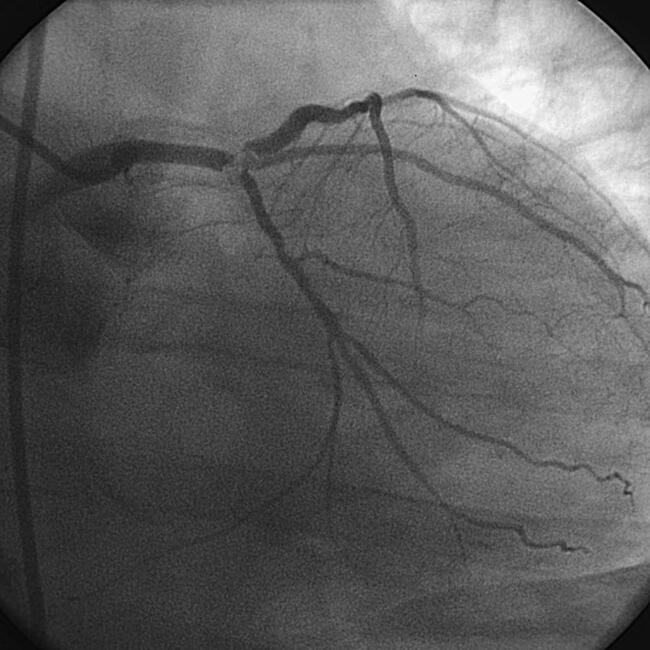

Figure. Cine angiogram frame in a 69-year-old man with angina at rest shows a severe distal left main trifurcation hazy narrowing involving the LAD and CFx (in 2001). The patient was sent to surgery, but likely could be a candidate for high-risk PCI today. The question of MCS in UPLM PCI remains open.